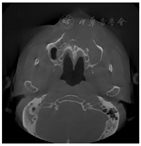

患者,男性,65岁,因反复发作上颌前牙区肿胀疼痛6年余。6年前出现上颌前牙区肿胀不适,开始时无明显疼痛,未治疗,2个月前再次发作,伴上前牙疼痛就诊,拍摄口腔CBCT发现上颌偏左侧大面积低密度影像,有不连续的骨间隔影,且累及左侧鼻底及鼻腔外侧壁(图1,图2,图3)。

口腔检查:口腔颌面部左右不对称,左侧鼻旁区明显隆起,按压乒乓球样感,双侧颞下颌关节无弹响,无压痛。口内见12-23前庭沟处膨隆,大小约4.2 cm×2.0 cm,边界清,质软,有轻微压痛,22-24腭侧球形膨隆,大小约1.5 cm×1.5 cm,边界清,质软,可触及波动感,无压痛。22唇侧有一瘘管,挤压有脓液溢出。鼻内镜检查:鼻腔黏膜略充血,左侧鼻底及下鼻道见明显隆起(图4),将左侧下鼻甲推向外上方,鼻中隔向右侧偏曲,左侧鼻道较宽敞,中鼻道略隆起,未见分泌物。CBCT示:12-24根尖区可见3.7 cm×1.6 cm大小的低密度影像,边界清楚,密度均匀,内见不完全的骨间隔影,肿物累及左侧鼻底及鼻腔外侧壁,左侧上颌窦内见液平面。